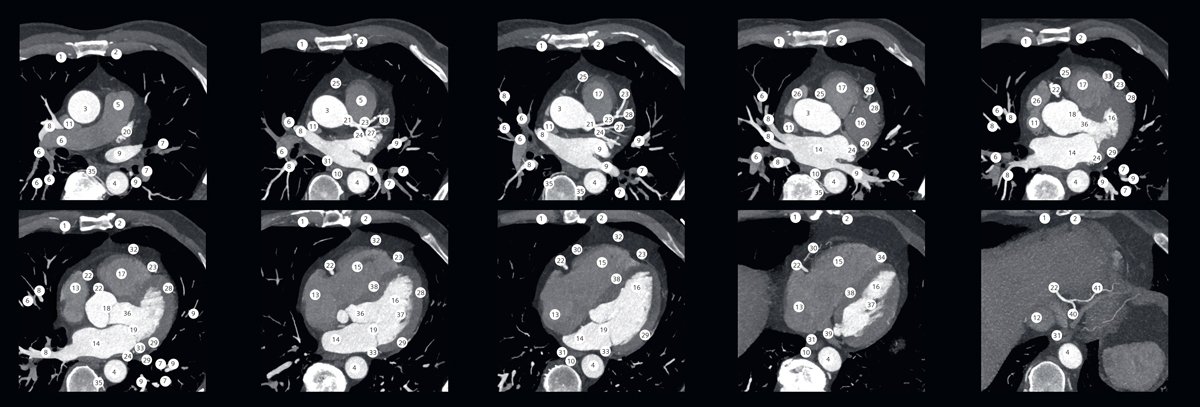

CT Cardiac Anatomy